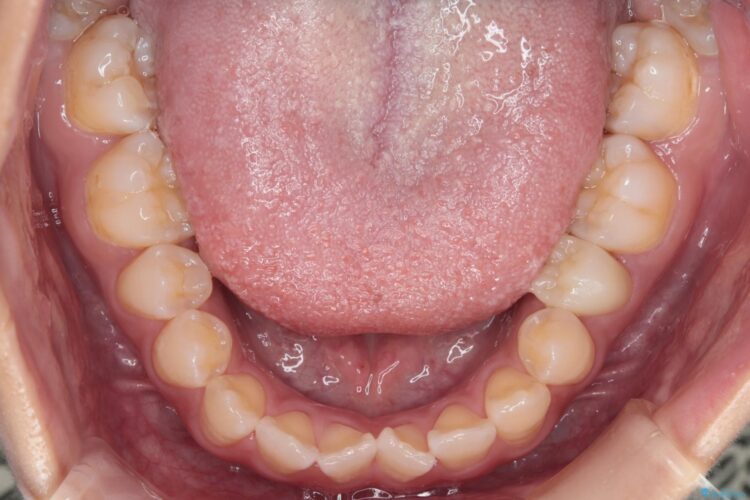

八重歯とガタつきが気になるとご来院された患者様です。

精密検査の結果、抜歯はせずIPR(歯と歯の間を削る処置)を行い、目立ちにくい審美ワイヤー装置にて歯列拡大を行うことで歯列を整える治療計画を立てました。